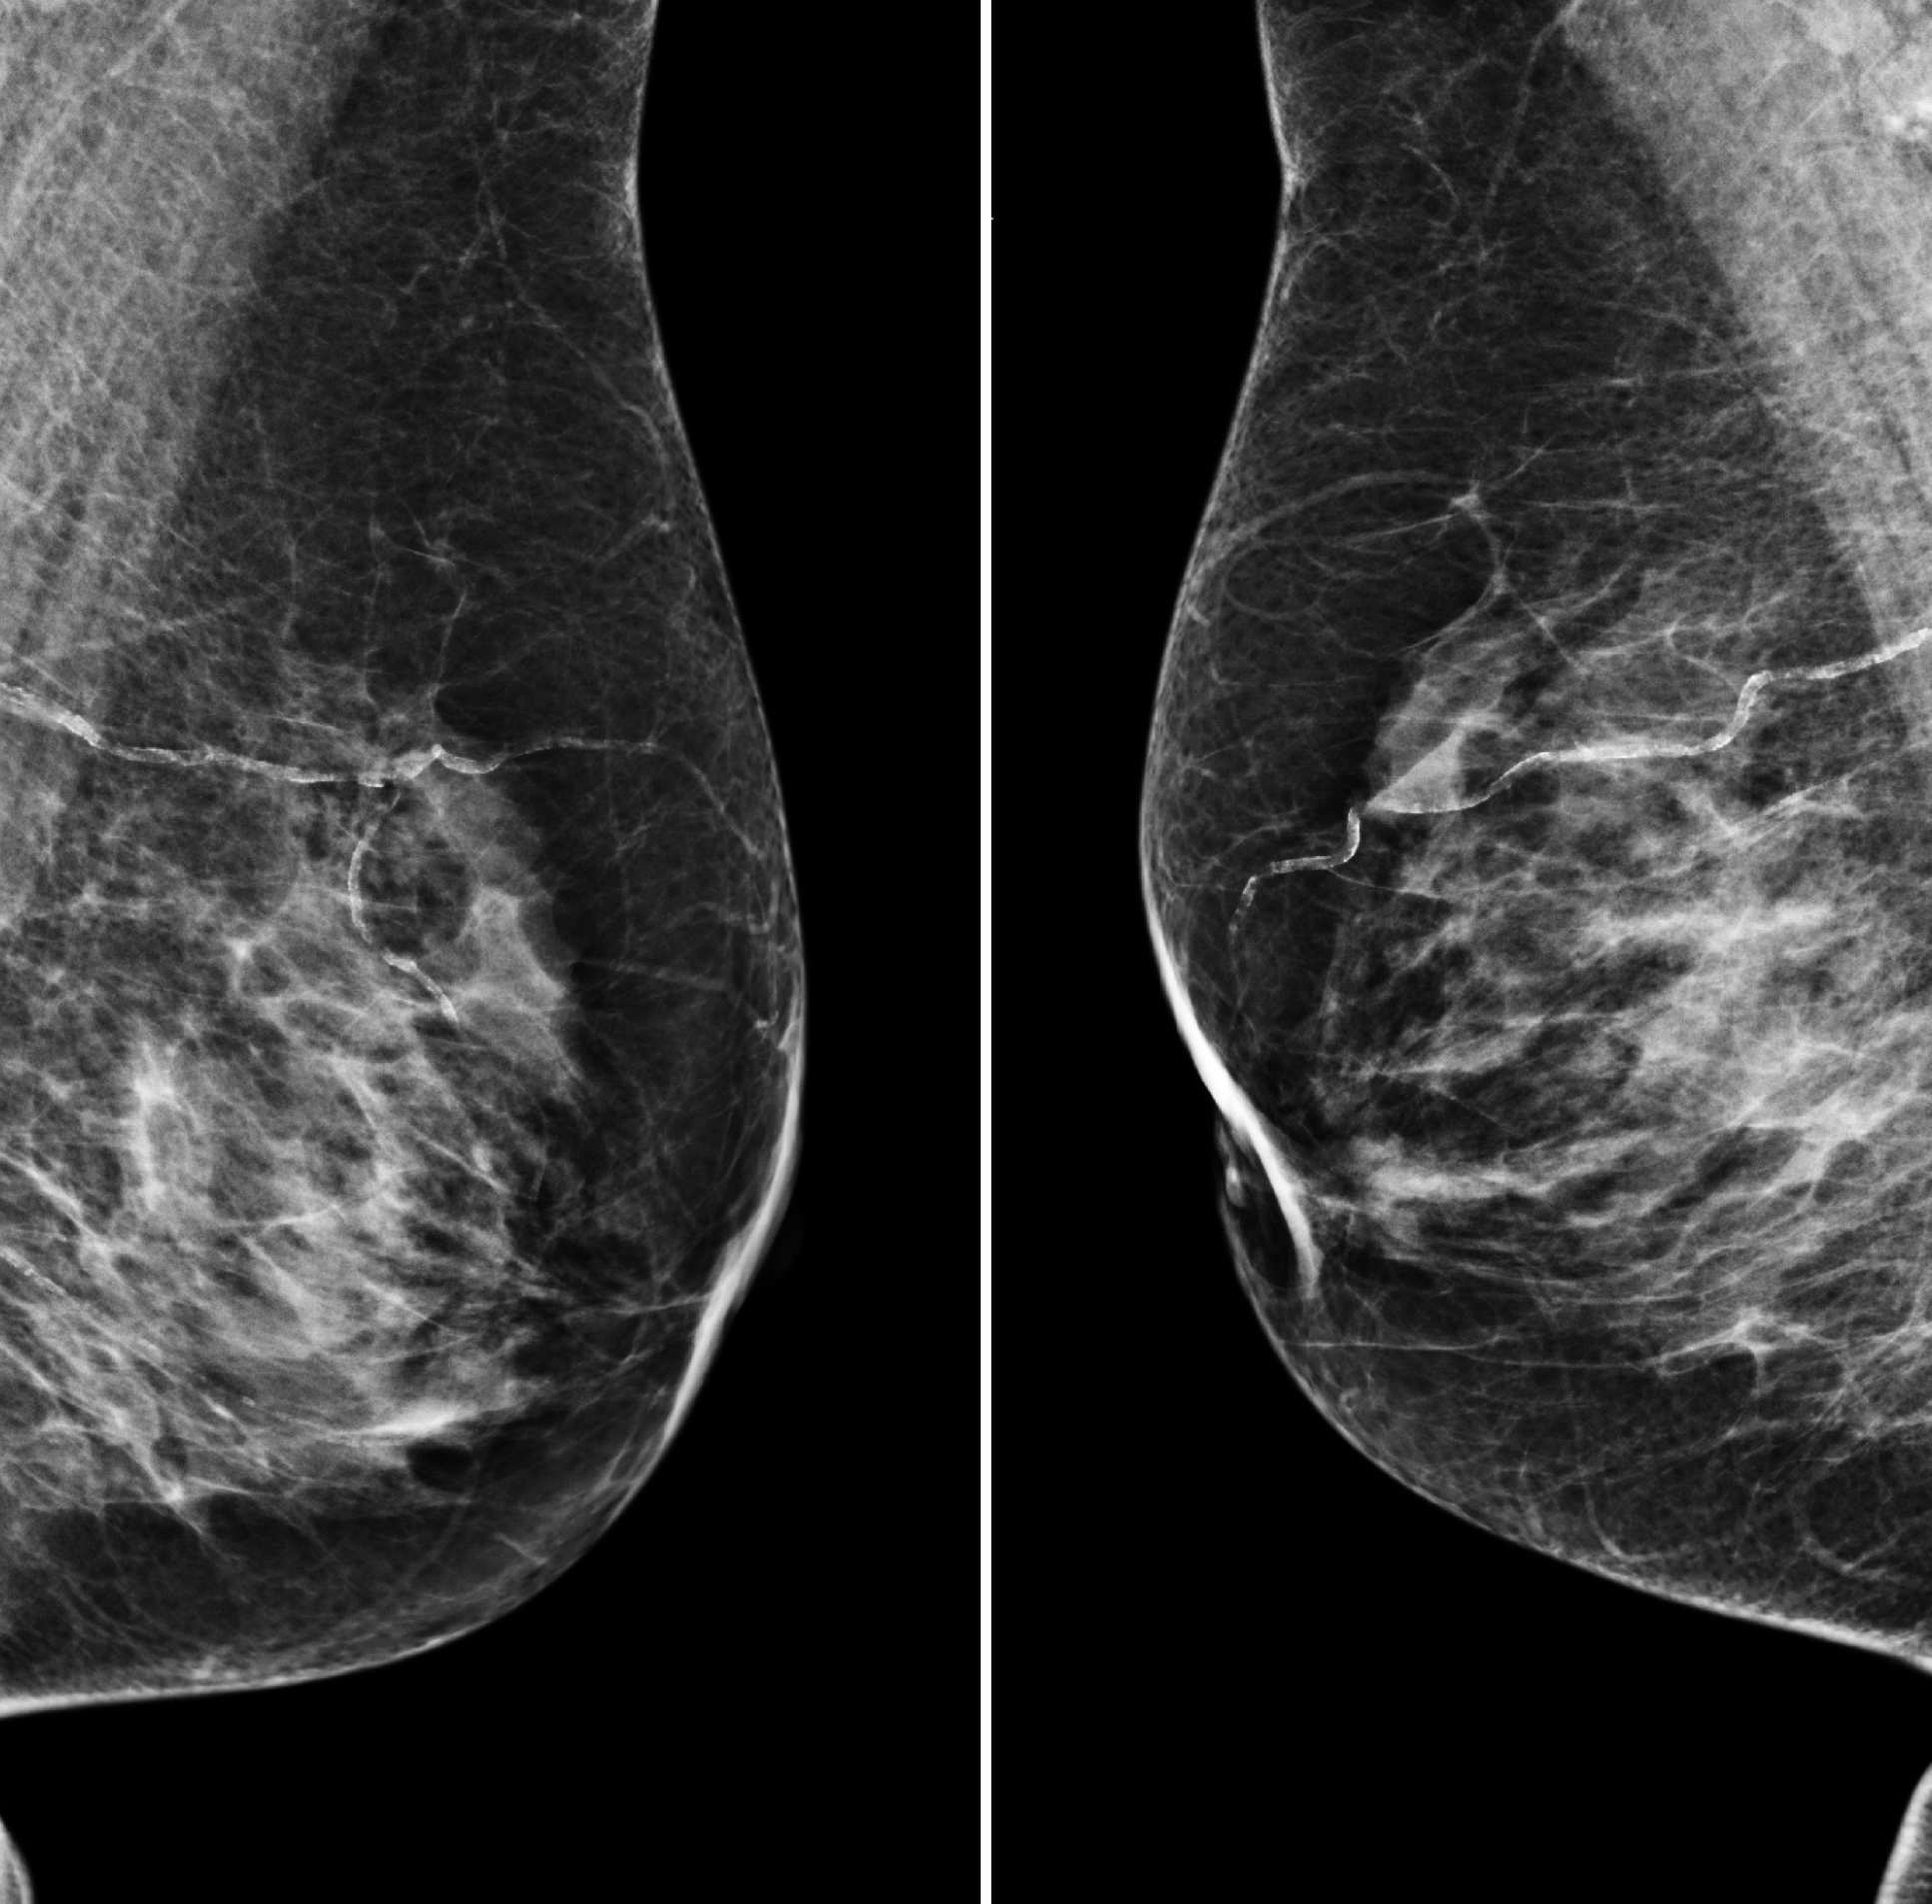

Image showing two mammograms side by side

The findings showed the AI was able to correctly identify cancers from images with a similar degree of accuracy to expert radiologists, and has the potential to support decision making and workload of clinical staff. (Images: The CRUK-funded OPTIMAM database)